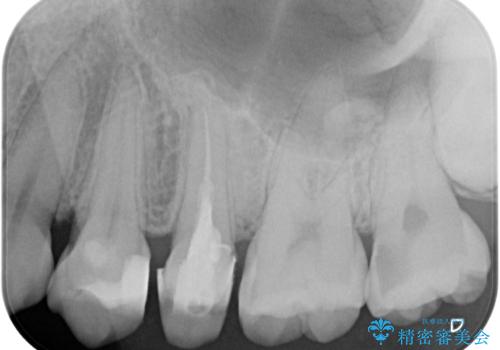

- 左上の前から5番目の金属の詰め物(メタルインレー)が取れたとのことで来院された患者様です。一時帰国中とのことで短期間での治療を希望されていました。土台はファイバーコアがしっかり入っていたため、そのまま利用することにしました。根管治療は症状もなく、レントゲン上でも病変を認めないため患者様と相談して根管治療を行わないことにしました。拡大鏡の視野下において、虫歯を除去して元々の詰め物の範囲も大きいためオールセラミッククラウンに適した形に整えました。

根管治療を施した歯は割れるリスクが上昇するため、詰め物(インレー)ではなく、被せ物(クラウン)にしなければなりません。